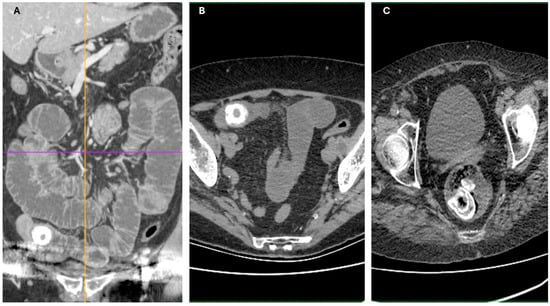

Imaging findings were consistent with biliary ileus, characterized by the presence of ectopic gallstones within the gastrointestinal tract. As shown in Figure 3A–C, axial and coronal CT images demonstrated radiopaque enteric gallstones. Figure 4 highlights a gallstone associated with a cholecystoduodenal fistula. Further axial and coronal sections (Figure 5A–C) show additional enteric gallstones, including one in the rectal ampulla.

Figure 4. Enteric gallstone associated with cholecystoduodenal fistula. Coronal reconstructed CT images showing an ectopic gallstone within the intestine, secondary to a cholecystoduodenal fistula—a classic radiological finding in biliary ileus. (AC) Coronal reconstructions showing multiple distended small bowel loops upstream from the obstruction site, with the intraluminal gallstone visible in the terminal ileum. Acquisition with 5 mm slice thickness and 3 mm reconstruction. Images have been cropped and zoomed for optimal visualization while maintaining the original scale; a 10 mm scale bar is included in each panel.